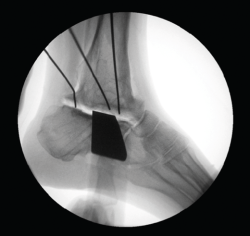

Figura 3. Impresión de la guía 3D con el defecto del astrágalo y guía para su colocación.

- Impresión 3D del defecto del astrágalo y guía para la colocación de las agujas (Figura 3).